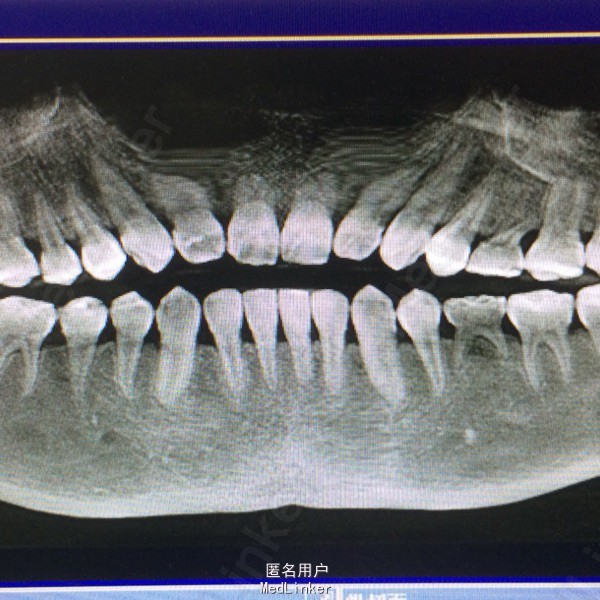

检查:18.28.38.48牙齿阻生,牙龈无红肿,65.75乳牙形态,冷(-),扣痛(-),不松,龈(-), 全口曲面断层片示:18,28.38.48牙齿阻生,根尖周未见明显异常,65.75乳牙,牙根不同程度吸收,25.35先天缺失 全口咬合关系基本正常

诊断:18.28.38.48牙齿阻生,65.75乳牙滞留,25.35先天缺失 建议:65.75观察,18.28.38.48分次拔除